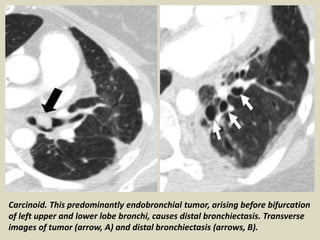

Endoluminal Obstruction by Tumor Most

carcinoid tumors are primarily endobronchial

lesions, occurring in the central, main, or

segmental bronchi. Some small tumors are

located entirely within the lumen. However,

some display a dominant extraluminal

component with only a small part of the

tumor lying within the airway (iceberg

lesion). A variety of other benign and

malignant neoplasms can also result in

obstruction leading to focal bronchiectasis.

Carcinoid. This predominantly endobronchial tumor, arising before bifurcation

of left upper and lower lobe bronchi, causes distal bronchiectasis. Transverse

images of tumor (arrow, A) and distal bronchiectasis (arrows, B).